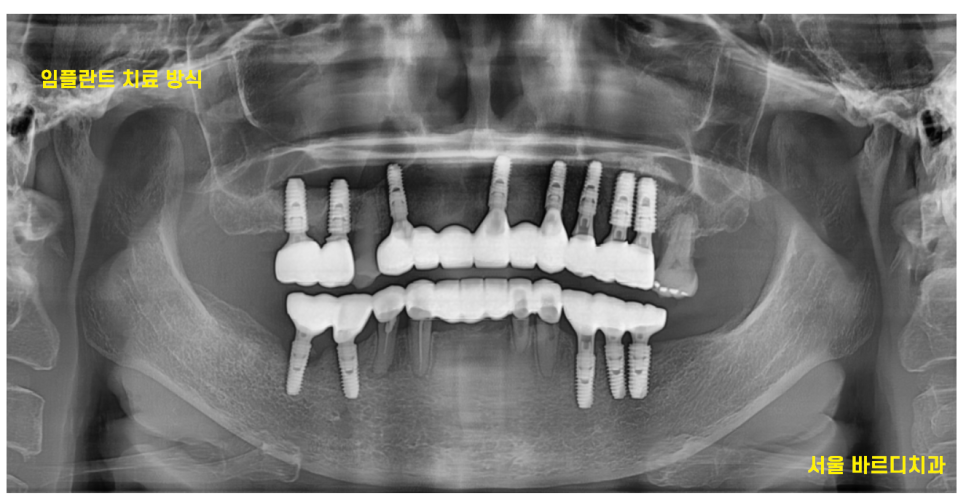

다수의 치아 상실

치아가 많이 상실된 상태였습니다.

1-2개 치아가 상실되었을 때는 임플란트로

다수 치아가 상실되었을 때는

틀니 치료도 고민해볼 수 있습니다.

24.04.30

그에 비하여 임플란트는 뼈에 고정 시키기 때문에

빠지지도 않고

편안하게 식사가 가능합니다.

결국은 길동 치과에서

임플란트로 치료 하셨습니다.